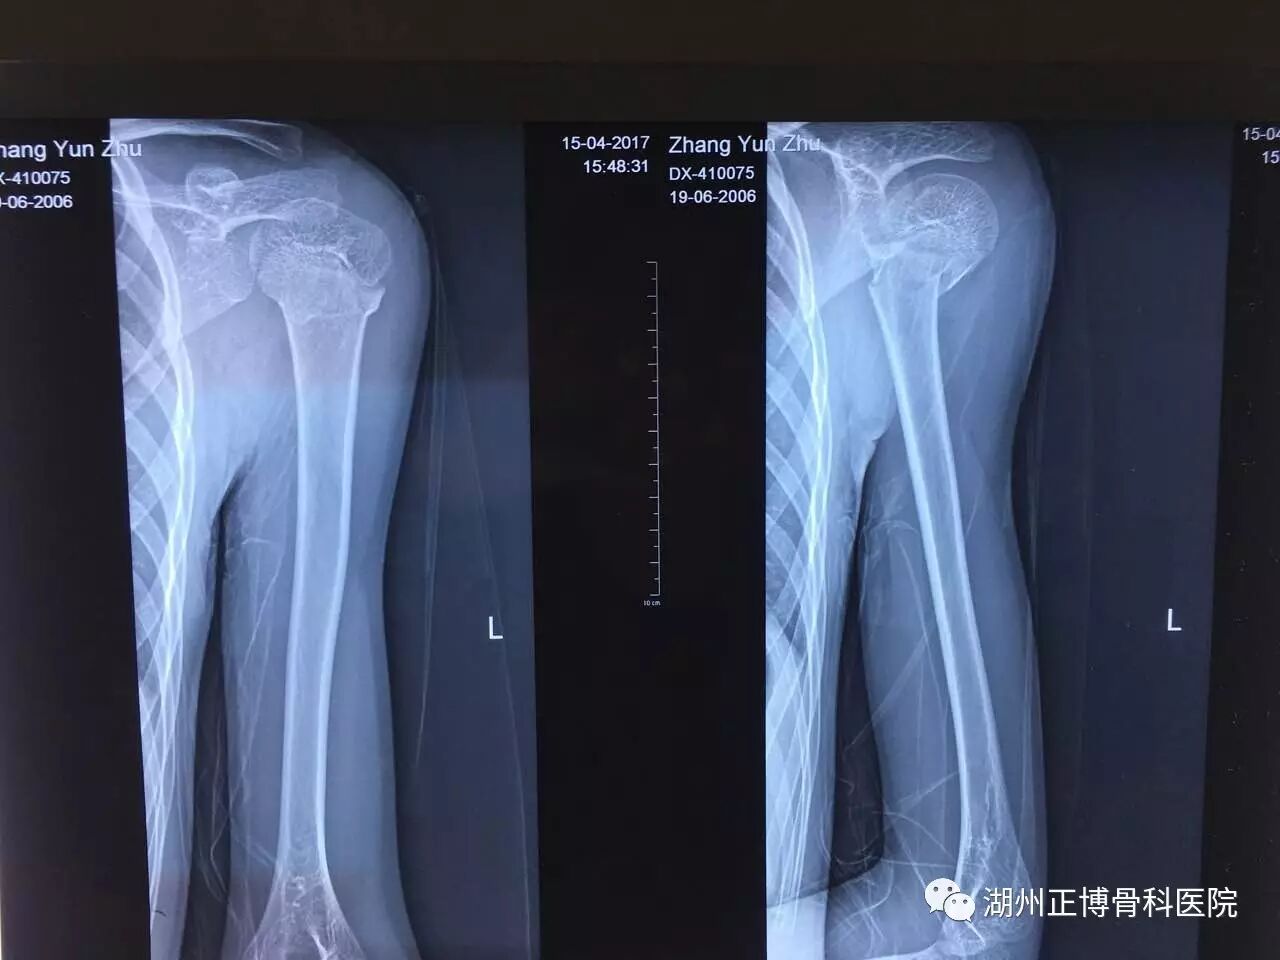

胳膊x光片图片,x光片图片全身

复位后的x光片,可惜美篇不支持手法复位视频

出事当天拍的x光片

骨折x光片图片